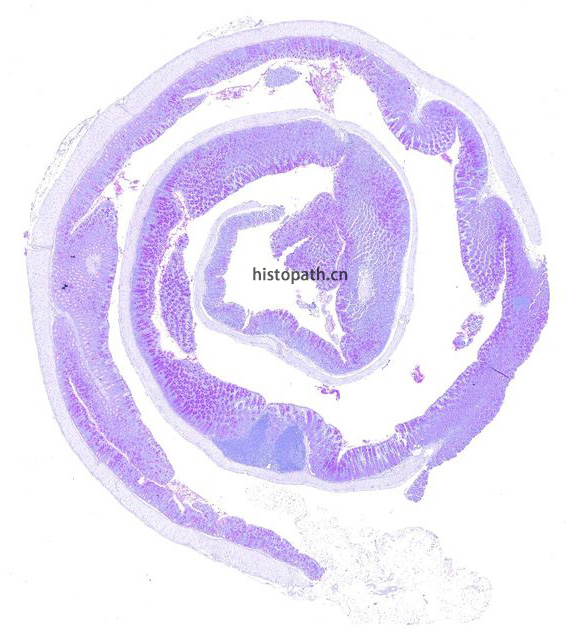

染色结果分析:糖原、多糖类物质及其他PAS反应阳性物质呈洋红色,细胞核呈蓝色。